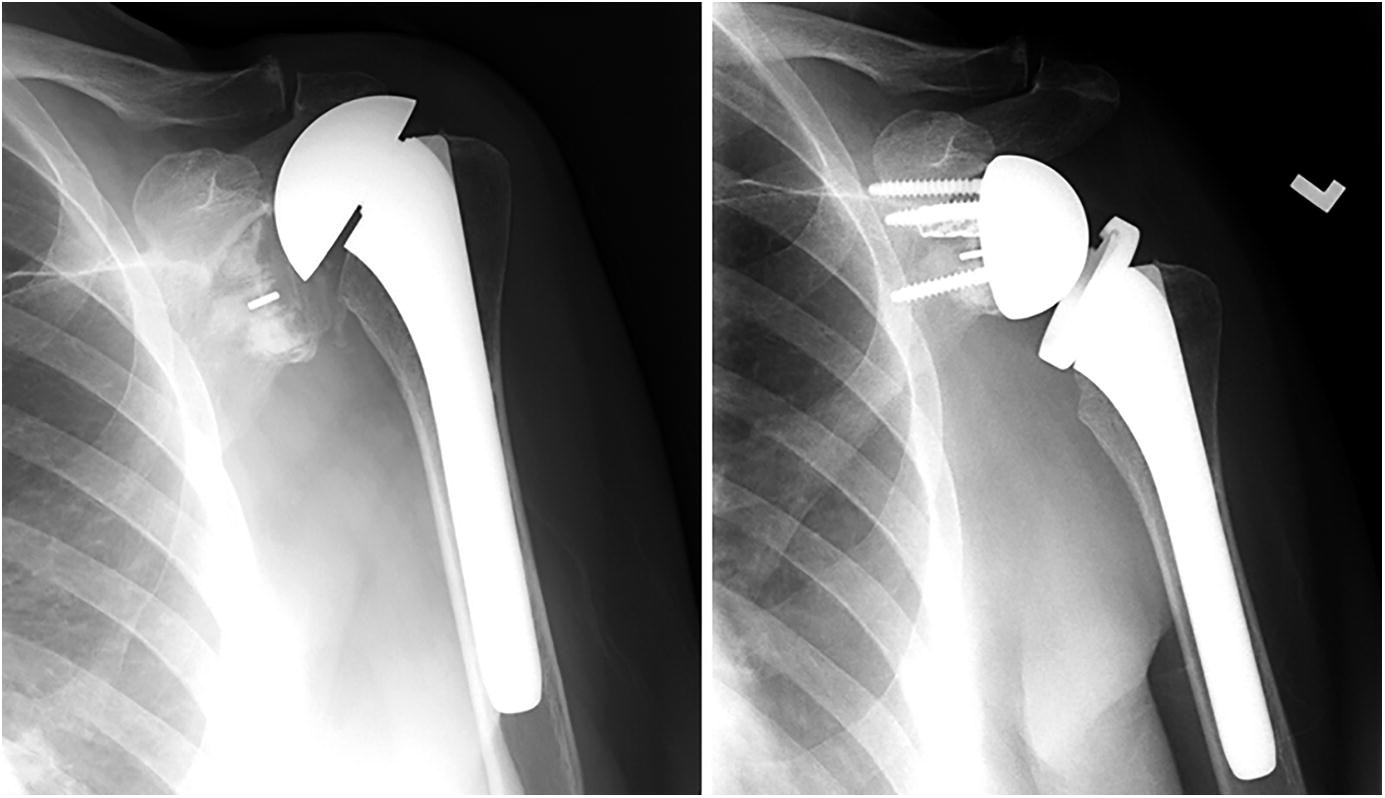

Shoulder and Elbow Surgery Revision of failed anatomic total shoulder

From www.researchgate.net

One case of revision reverse total shoulder arthroplasty severely What Is A Shoulder Revision Surgery Patients will be positioned to allow all possible. Shoulder replacement surgery is an operation to replace your damaged shoulder joint with an artificial joint. In fact, any type of surgery, particularly joint replacements, can require what is known as “revision surgery.” “revision surgery is any surgery that, for whatever reason, needs to be redone. Surgery after a prior total shoulder. What Is A Shoulder Revision Surgery.